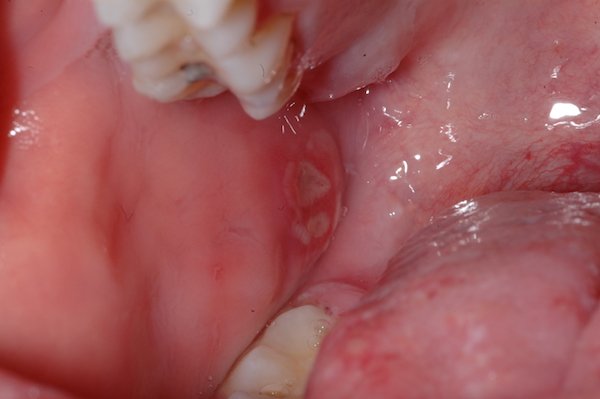

La si distingue facilmente dalla stomatite aftosa poichè interessa la quasi interezza della bocca associandosi a febbre fino a 40 gradi, nausea, gonfiore delle gengive brividi cefalee linfonidi ingrossati dolore e bruciore molto più forti e maggior numero di lesioni (vescicole a grappolo o lesioni tondeggianti di maggior dimensione contenenti un liquido sieroso limpido che una volte rotte portano ad ulcerazioni superficiali)sia sulla lingua sia sulla gengiva sia sul palato sulle labbra e sulla mucosa delle guance